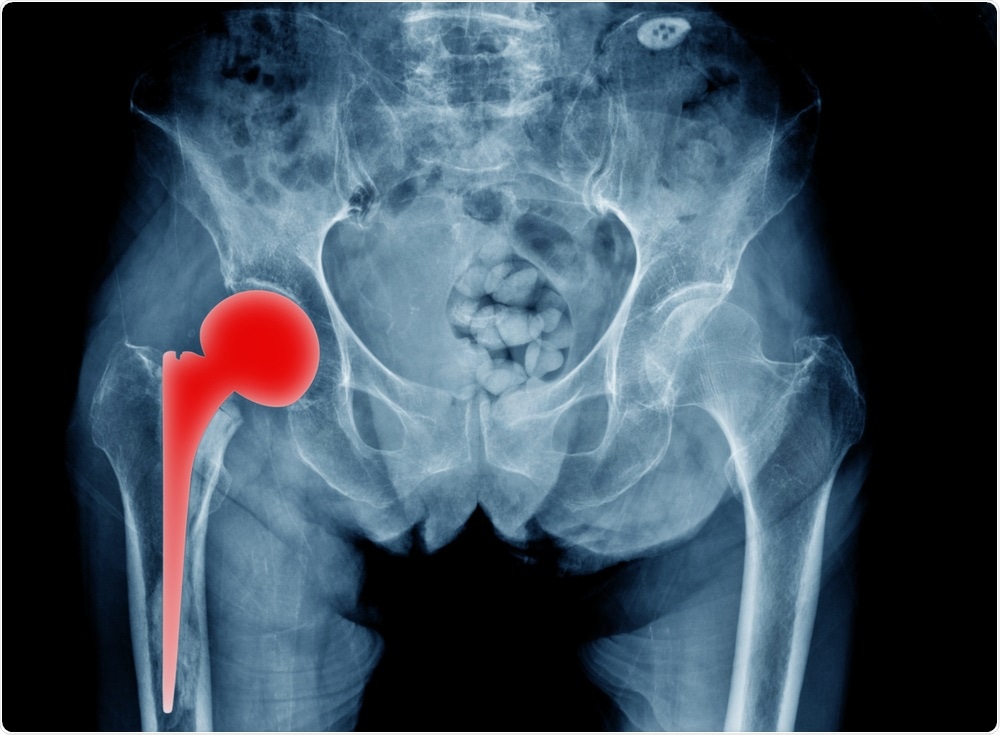

Titanium hip replacement - x ray of patientTridsanu Thopet | Shutterstock